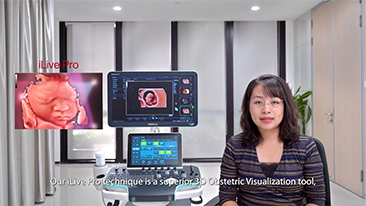

Didukung oleh platform ZST+ yang canggih, solusi cerdas yang lengkap dari Nuewa dirancang secara khusus untuk mendukung kesehatan kaum wanita yang lebih baik selama masa prakehamilan, kehamilan, dan pemulihan pascapersalinan, untuk menghasilkan diagnosis yang komprehensif dan efisien guna memenuhi tantangan klinis yang semakin meningkat.

Wawasan